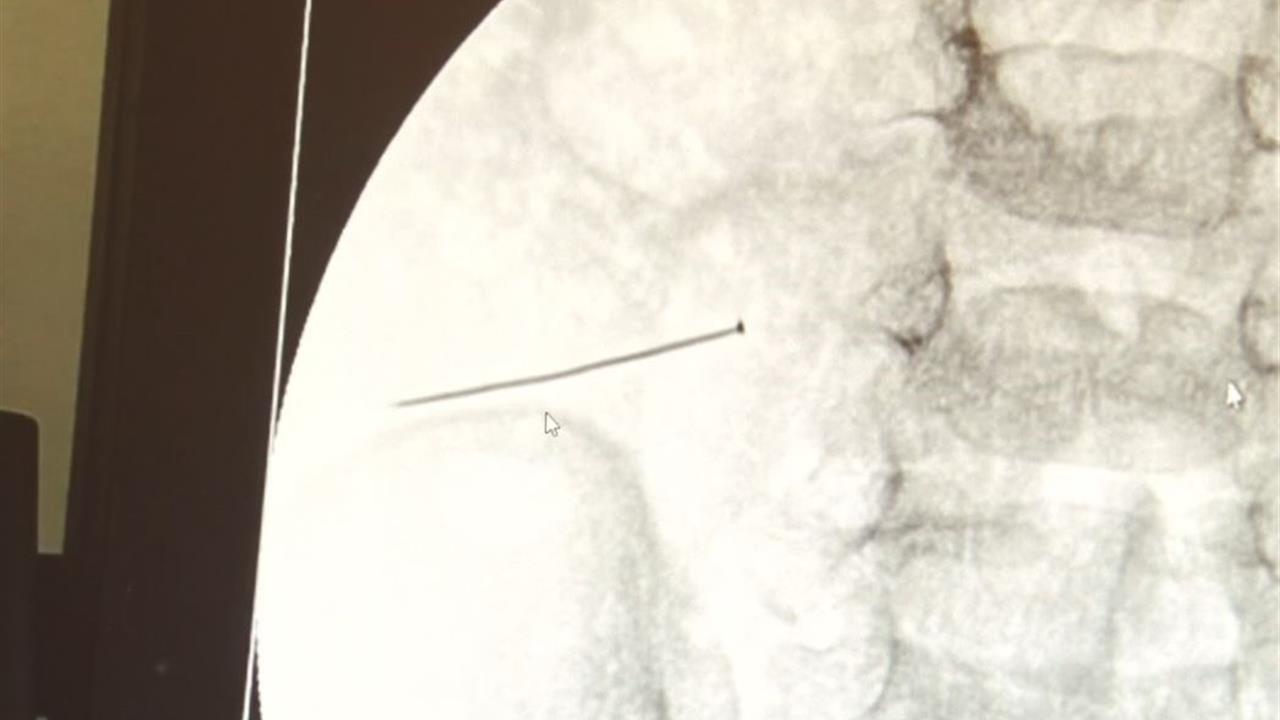

İstanbul'da 2 yaşındaki bir çocuğun bağırsağından 3 santim uzunluğunda bir iğne çıkarıldı. Çocuk, şiddetli karın ağrısı ve kusma ile hastaneye başvurdu. Yapılan ameliyatla iğne başarıyla çıkarıldı.

İstanbul'da 2 yaşındaki bir çocuk, şiddetli karın ağrısı ve kusma şikayetiyle hastaneye getirildi. Yapılan tetkiklerde, çocuğun bağırsağında 3 santimlik bir toplu iğne bulunduğu tespit edildi. Çocuğun durumu, ince bağırsakta meydana gelen delinmeyle ciddi bir hal aldı. Doç. Dr. Sefa Sağ, bu tür yabancı cisimlerin yutulmasının tehlikelerine dikkat çekerek, soluk borusuna kaçması durumunda ölümle sonuçlanabilecek ciddi sonuçlar doğurabileceğini belirtti. Ameliyat, yaklaşık 1 saat sürdü ve başarılı bir şekilde tamamlandı. Ayrıca, çocukların evdeki tehlikelerden korunması için temizlik maddelerinin güvenli bir yerde saklanması gerektiği vurgulandı. Doç. Dr. Sağ, ev kazalarının önlenmesi için ailelerin dikkatli olması gerektiğini ifade etti.